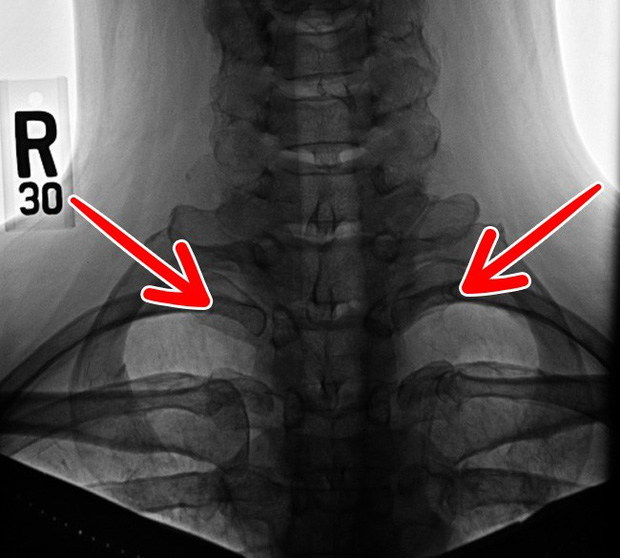

5. Xương sườn cổ

Khoảng 1% dân số thế giới có nhiều xương sườn hơn bình thường, kéo cả lên khu vực gần cổ. Theo Thuyết tiến hóa thì đây có thể là những gì còn sót lại từ thời kỳ khủng long lận, nhưng giờ thì chẳng còn tác dụng gì ngoài việc khiến chúng ta căng thẳng hơn và dễ gây bệnh về thần kinh.